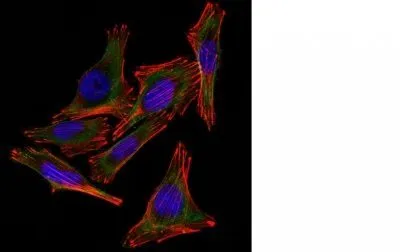

- Description: S100 belongs to the family of calcium binding proteins. S100A and S100B proteins are two members of the S100 family. S100A is composed of an alpha and a beta chain whereas S100B is composed of two beta chains. This antibody is specific against an epitope located on the beta-chain (i.e. in S-100A and S-100B) but not on the alpha-chain of S-100 (i.e. in S-100A and S100A0). This antibody can be used to localize S-100A and S-100B in various tissue sections. S-100 protein has been found in normal melanocytes, Langerhans cells, histiocytes, chondrocytes, lipocytes, skeletal and cardiac muscle, Schwann cells, epithelial and myoepithelial cells of the breast, salivary and sweat glands, as well as in glial cells. Neoplasms derived from these cells also express S-100 protein, albeit non-uniformly. A large number of well-differentiated tumors of the salivary gland, adipose and cartilaginous tissue, and Schwann cell-derived tumors express S-100 protein. Almost all malignant melanomas and cases of histiocytosis X are positive for S-100 protein._x000D__x000D_Primary antibodies are available purified, or with a selection of fluorescent CF® Dyes and other labels. CF® Dyes offer exceptional brightness and photostability. Note: Conjugates of blue fluorescent dyes like CF®405S and CF®405M are not recommended for detecting low abundance targets, because blue dyes have lower fluorescence and can give higher non-specific background than other dye colors.

- Cellular Locus: Cytoplasmic|Nucleus|Vesicular

- Applications: IF (verified) | IHC, FFPE (verified)

- Validated Applications: IF, IHC, FFPE

- Additionnal Information: Higher concentration may be required for direct detection using primary antibody conjugates than for indirect detection with secondary antibody|Immunofluorescence: 1-2 ug/mL|Immunohistology formalin-fixed 0.25-0.5 ug/mL|Staining of formalin-fixed tissues requires boiling tissue sections in 10 mM citrate buffer, pH 6.0, for 10-20 min followed by cooling at RT for 20 minutes|Flow Cytometry 0.5-1 ug/million cells/0.1 mL|Western blotting 0.5-1 ug/mL|Optimal dilution for a specific application should be determined by user